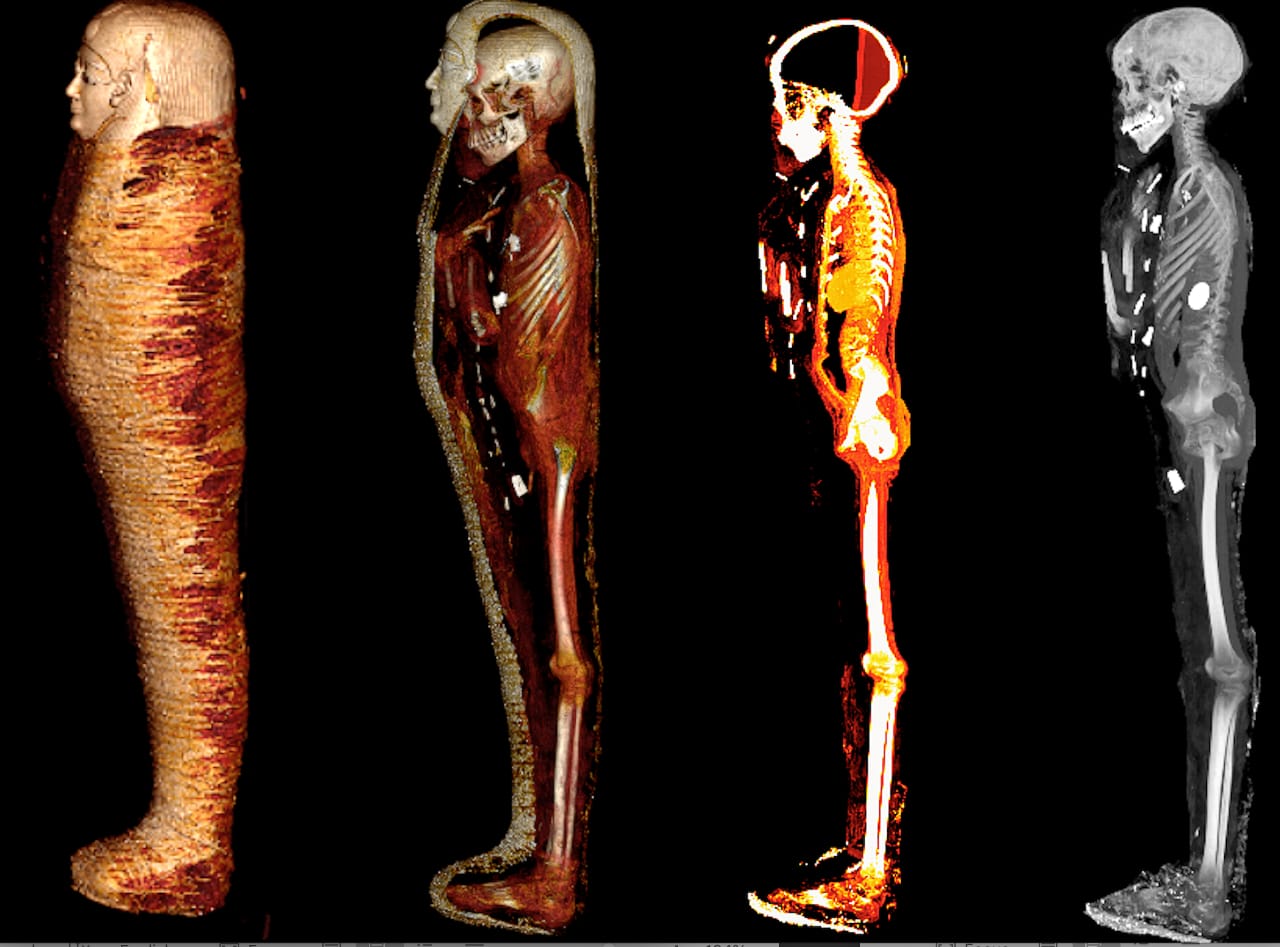

وأوضحت الدكتورة سحر سليم، أن المومياء لصبي توفي عن عمر يناهز 15 عام وأنه تم تحنيطها بإتقان كبير، وتم إزالة المخ من خلال فتحة الأنف ووضع الحشوات والراتنج داخل تجويف الجمجمة، كما تم إزالة الأحشاء من خلال شق صغير أسفل البطن ووضع الحشوات والراتنج بداخل الجسم، بينما حرص المحنطون علي الإبقاء علي القلب الذي تم رؤيته في صور الأشعة بداخل تجويف الصدر.

وأضافت سحر سليم، إلى أن الأشعة أوضحت ما بداخل اللفائف حيث ترتدي المومياء ترتدي قناعًا ذهبيًا وصدرية مصنوعة من الكارتوناج وصندلًا من النسيج.

وأكدت الدكتورة سحر سليم أن الدراسة كشفت عن وجه المومياء لأول مرة بعد إزالة اللفائف بشكل افتراضي بتقنية الأشعة المقطعية، حيث أتاحت الدراسة فرصة فريدة لاكتشاف أسرار تحنيط المومياء دون المساس باللفائف، وكما تركها المصريين القدماء.